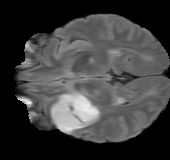

As we observe from the right image in Fig. 2, our BRM, both from MIMO and SISO settings, predicts the performance of dedicated models with a high correlation. We further choose the best three , and perform the last stage of fine-tuning accordingly to (6). A visual evaluation on real data is shown in Fig. 3. For simulated data, please refer to the Supplemental Material section.

Base on the best performing , we perceive that among , , and FLAIR, the results are best when is sampled the most. We suggest that this makes intuitive sense as images provide the best contrast out of the three sequences, which can compensate for the details lost in other images. The same observation can be made on the simulated data, where both and FLAIR show good contrast. When the time setting is changed to non-uniformity, we can see that our search for the best sampling strategy reflects the change. is sampled more as a result of faster acquisition time, while is still sufficiently sampled.

| Sequence | LR | SISO | MIMO | MIMO tuned | GT |

|---|---|---|---|---|---|

|

(k) 39.89/0.9311

(k) 39.89/0.9311

|

(l) 43.94/0.9864

(l) 43.94/0.9864

|

(m) 44.74/0.9883

(m) 44.74/0.9883

|

(n) 45.49/0.9894

(n) 45.49/0.9894

|

(o) PSNR/SSIM

(o) PSNR/SSIM

|